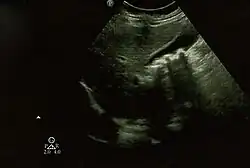

Biliary pseudolithiasis as seen on ultrasonography. The gallbladder contains gallstone mimics resulting from ceftriaxone therapy.

Biliary pseudolithiasis is an unusual complication of ceftriaxone where the drug complexes with calcium and mimics gallstones.[1][2] It is reversed when ceftriaxone administration is stopped.[2] It was first described in 1988 by Schaad et al. as "reversible ceftriaxone-associated biliary pseudolithiasis".[2][3] Ceftriaxone has been frequently associated with biliary sludge or biliary pseudolithiasis in subsequent reports.[3] Ceftriaxone is excreted primarily through the urine, but also through the bile, up to 40% of its excretion, with concentrations in the bile 20-150 times higher than in the serum.[3][4] It forms a calcium salt in the gallbladder, which can exceed its solubility and create precipitates that resemble gallstones on ultrasonography.[3] The incidence of pseudolithiasis in children treated with ceftriaxone is up to 25%, but most patients are asymptomatic.[3][4] Risk factors for biliary pseudolithiasis include age greater than 24 months, gram-negative sepsis, high doses of ceftriaxone, hypercalcemia, surgery, and decreased bile flow/increased ceftriaxone excretion in bile.[3][4][5] Conservative management with serial ultrasounds is recommended until the "stones" completely resolve.[3] If associated with ceftriaxone, it resolves on average about 2 weeks after the ceftriaxone is stopped.[4]